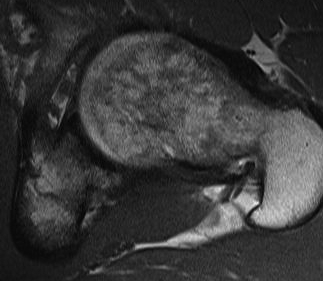

MRI alpha angle

CT

Cam impingement